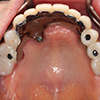

2.固定物埋入的手术

经过手术将类似牙根形态的植入体植入(上下)颚的骨组织内,(fixture)。手术会进行局部麻醉,可以放心接受手术。